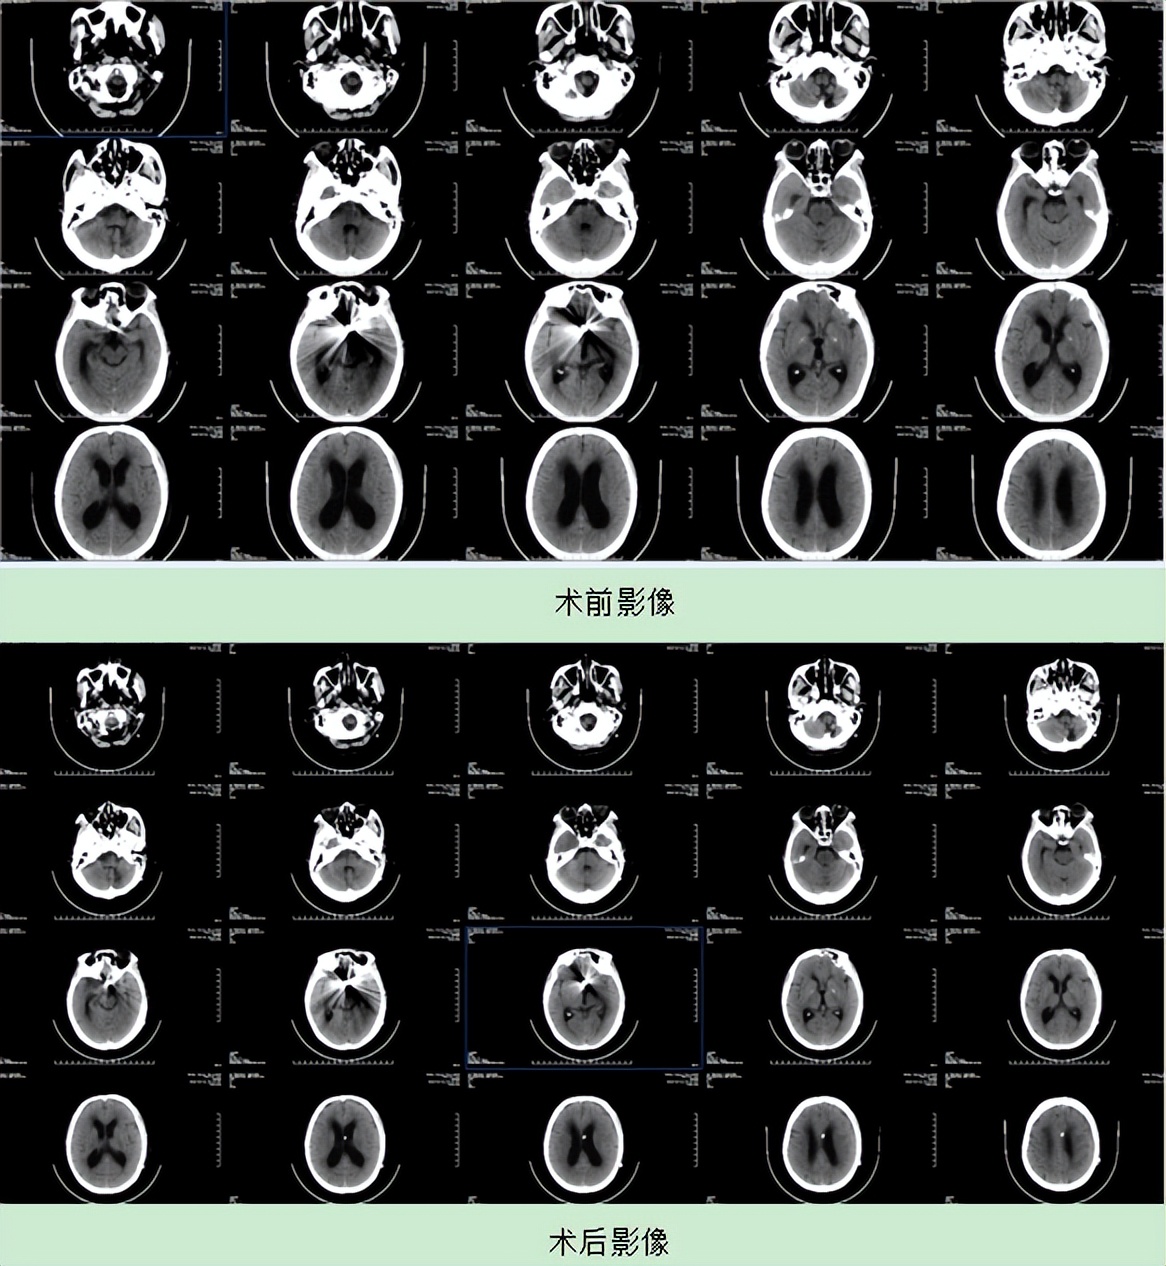

患者入住我院后,头颅CT提示脑积水改变,经过系列检查诊断为:脑积水;颅内动脉瘤术后;颅内动脉瘤破裂伴蛛网膜下腔出血;左锁骨下动脉狭窄;高脂血症。

3月10日,在各科室周密的术前准备下,由傅先明教授专家团队、脑血管中心谢英贺主任主刀,在全麻下为患者实施“侧脑室腹腔内分流术”。手术采用头部钻孔,植入引流管,经头部、颈部、胸部皮下将导管引流到腹腔,使脑脊液引流到腹腔内吸收,以缓解脑室内的压力,从而使头痛缓解或消失,使脑功能得以好转和恢复。经过一个多小时的努力,手术顺利完成。